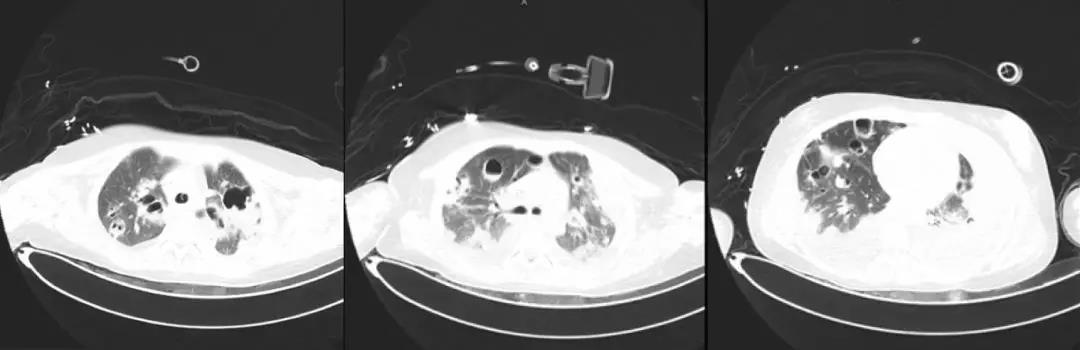

*影像学仍持续变化:

左侧胸腔病变为肺大泡?气胸?如何处理?药物是否需要调整?